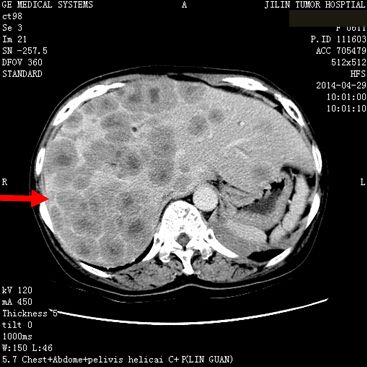

患者任某,女,60岁,患者因刺激性咳嗽3个月,右上腹部疼痛2个月于2014年4月11日就诊。入院后行肺增强CT、全腹增强CT;:左肺下叶支气管开口周围见类圆形肿块影,大小约为4.75×4.54cm,肿块包绕左肺下静脉及左肺下动脉干,肿块不均匀强化,左肺下叶支气管开口截断,左肺下叶内前基底段肺组织实变。左肺门见肿大淋巴结与肺门肿块融合。肝脏大小及形态未见确切异常,肝实质内弥漫性分布低密度肿块影,肿块融合成团,约占据整个肝脏,增强检查环形强化,选择病灶2.81×2.68cm,腹腔内见多个肿大淋巴结,融合成团,包绕邻近组织,较大约为3.21×2.57cm,左侧肾上腺见类圆形肿块影,大小约为2.49×1.99cm,增强检查略强化。明确诊断为:左肺下叶小细胞肺癌(T2aN1M1b)Ⅳ期,广泛期、左肺门淋巴结转移、 多发肝转移、腹腔淋巴结转移。符合我院正在进行的Ipilimumab联合EP治疗广泛期小细胞肺癌的III期临床研究,给予入组。于2014年5月1日开始给予EP方案化疗(VP-16,100mg/m2,157mg,d1-3;DDP,75mg/m2,118mg,d1),共给予化疗4周期,第3周期开始给予加用Ipilimumab单抗(10mg/kg),现患者已应用2周期,无明显严重不良反应发生。2周期后疗效判定:靶病灶1、左肺内病灶消失,2、左肾上腺转移病灶11.6×9.5=110.2,3、肝转移病灶11.3×9.1=102.83。靶病灶乘积之和213.03,疗效判定PR,非靶病灶:1、肝内其他转移病灶,存在,2、腹腔其他转移淋巴结,存在,疗效判定SD,总体疗效判定PR。现患者仍在继续用药中。

2014年4月29日治疗前